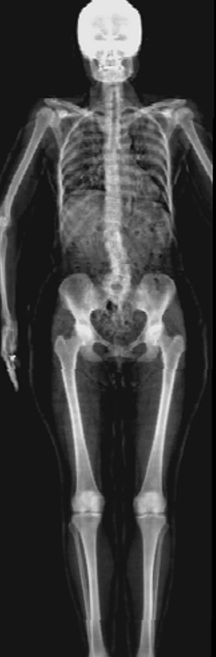

UK Biobank. A more comprehensive dataset of 48,384 full-body MRIs from more than 500,000 volunteers[67], capturing diverse physiological attributes across a broad demographic spectrum. These Dixon MRIs do not come stitched, the scans are scanned axially and there is a disparity in the bias field effect (a common artifact of MRI machines) which is strongest at the knee region. The same knee pattern is present on all samples in the dataset. UK Biobank MRIs are resampled to be isotropic and cropped to a consistent resolution (501 160 224). 48,384 whole-body MRIs are paired with antero-posterior (AP) DXA scans of the same subjects.

Notably, X-Diffusion achieves state-of-the-art dB for a few input slices while baselines require more than 60 input slices to achieve similar performance (Figure 7). The margin is more than 12 dB PSNR for the 1-slice input in both the BRATS and the UK Biobank benchmarks (see Table 1 and Figure 6). For reference, two randomly sampled MRIs from UK Biobank would have a PSNR of 15.95 dB 0.36 (on 4800 randomly sampled examples). Omitting the preprocessing step of alignment DXA to MRI, leads to a drop of PSNR on average by 2.87 dB (29.01 dB 26.14 dB). The slices from 3D reconstructed volumes at varying depths and axis of rotation, visually match the ground truths for both brain and whole-body scans (see Figures 4 and 5 left). We also plot the error map (Figure 3) and the spread of the error (Figure 5 right) of such X-Diffusion generations to highlight the differences with the ground truth MRIs.

Preservation of Spine Curvature. For the spine segmentation on UK Biobank, we use a UNet++ model [83] with Dice Loss. We use a model trained to predict curves on DXA on UK Biobank [11]). We measure the Pearson correlation factor [11] of spine curvature measured on the generated MRIs where the input is a single MRI coronal slice, a single sagittal slice, or from the paired DXA, against the curvature of reference real MRIs of the same samples. The correlation coefficients are 0.89 for the coronal MRIs, 0.88 for the sagittal MRIs, and 0.87 for the DXAs on the test set of 308 human-annotated angles. We can then bin the curvature of the spines under different scoliosis categories based on human-annotated angles: mild: , moderate: , and severe . We show the results in Figure 8. This illustrates that the generated MRIs preserve the spine curvature from normal to severe scoliosis cases. Additional details about spine curvature are provided in supplementary material.